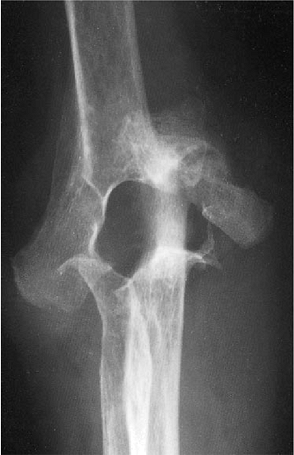

rheumatoid arthritis, fracture of the medial supracondylar column is

not uncommon and is not considered a significant event. This has

occurred in approximately 5% of our patients. If the column is

extremely thin, we simply excise the fragment. Otherwise, the fragment

is secured to the implant with a No. 5 Mersilene suture. We do not

alter our postoperative course as a result of this occurrence, as no

adverse effects have been appreciated as a result of this to date.

was treated with semiconstrained total elbow replacement. The Mayo

Modified Coonrad implant was selected for stability and because of the

favorable long-term results (Fig. 18-47). At 5 years the patient is pain free, has an arc of motion of 25 to 135 degrees, and shows no evidence of loosening (Fig. 18-48).

Figure 18-46. Severe rheumatoid arthritis with grade IV radiographic changes (severe architectural distribution).